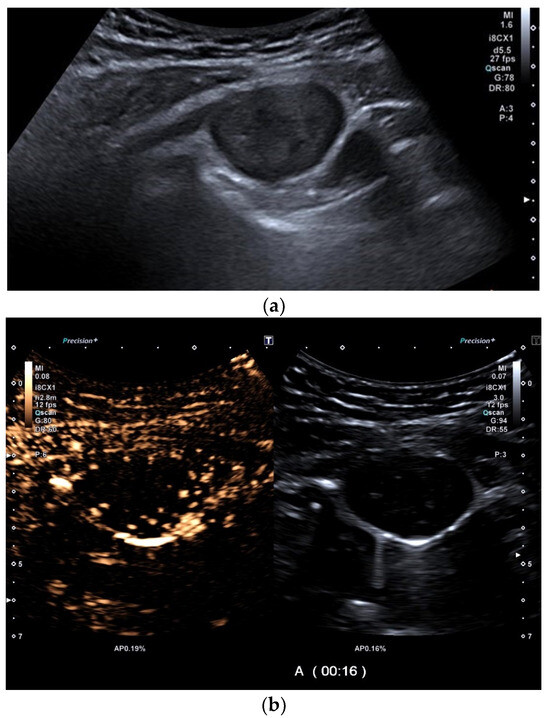

| Empyema | Hypoechoic thickened pleura, internal echos in the pleural effusion, hypoechoic pus, hyperechoic gas reflexes, fibrin strands, and chambering. In the phase of organization, thickened pleura, chambering of the pleural space. |

| Empyema necessitans | Exceeds the parietal pleura and infiltrates the surrounding soft tissue and chest wall muscles. |

| Tuberculous pleuritis | Pleura effusion with fibrin strands, pleural calcification, and thickening. Hypoechoic granulomatous inflammation and granulomas with hyper-enhancement on CEUS in thickened pleura. Hypoechoic caseous abscesses in thickened pleura, hypo- or nonenhanced, heterogeneously enhanced lesions, with contrast-enhanced septations and contrast-enhanced rim. |